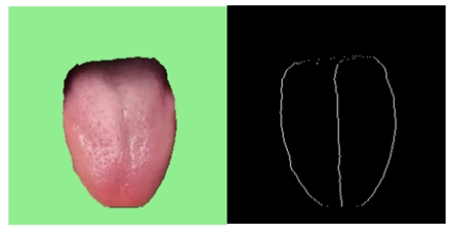

(1)用户上传的舌象图片已经被分割完成;

首先是要将舌象图片进行舌体分割(参照计算机视觉智能中医(三):基于Unet模型的舌头舌体图片分割)

舌体胖瘦分析的主要的对象是中下舌位,上舌位会影响分析的准确性,因此取舌体轮廓标记点的下0.75舌位。示意图如下图所示:

对下0.75舌位标记像素点进行舌体轮廓的多项式曲线拟合。由于分析的是曲线的“胖瘦”,因此多项式曲线的奇数次项影响较小,且项数较大较好。权衡模型的运行效率,中e诊采用4次项多项式曲线拟合。进行多张图片拟合的确定系数(R-square=SSR/SST)为0.82~0.95,说明4次多项式曲线拟合效果较好。舌体轮廓4次多项式拟合示意图如下: